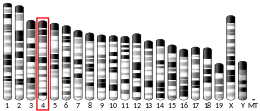

| Aliases | CGA, CG-ALPHA, FSHA, GPHA1, GPHa, HCG, LHA, TSHA, Chorionic gonadotropin alpha, glycoprotein hormones, alpha polypeptide, Alpha subunit of glycoprotein hormones, GPA1 | ||||||||||||||||||||||||||||||||||||||||||||||||||

| External IDs | OMIM: 118850 MGI: 88390 HomoloGene: 587 GeneCards: CGA | ||||||||||||||||||||||||||||||||||||||||||||||||||

Glycoprotein hormones, alpha polypeptide is a protein that in humans is encoded by the CGA gene.[5]

The gonadotropin hormones, human chorionic gonadotropin (hCG), luteinizing hormone (LH), follicle-stimulating hormone (FSH), and thyroid-stimulating hormone (TSH) are heterodimers consisting of alpha and beta subunits (also called chains) that are associated non-covalently. The alpha subunits of these four human glycoprotein hormones are identical; however, their beta chains are unique and confer biological specificity. The protein encoded by this gene is the alpha subunit and belongs to the glycoprotein hormones alpha chain family.[6]